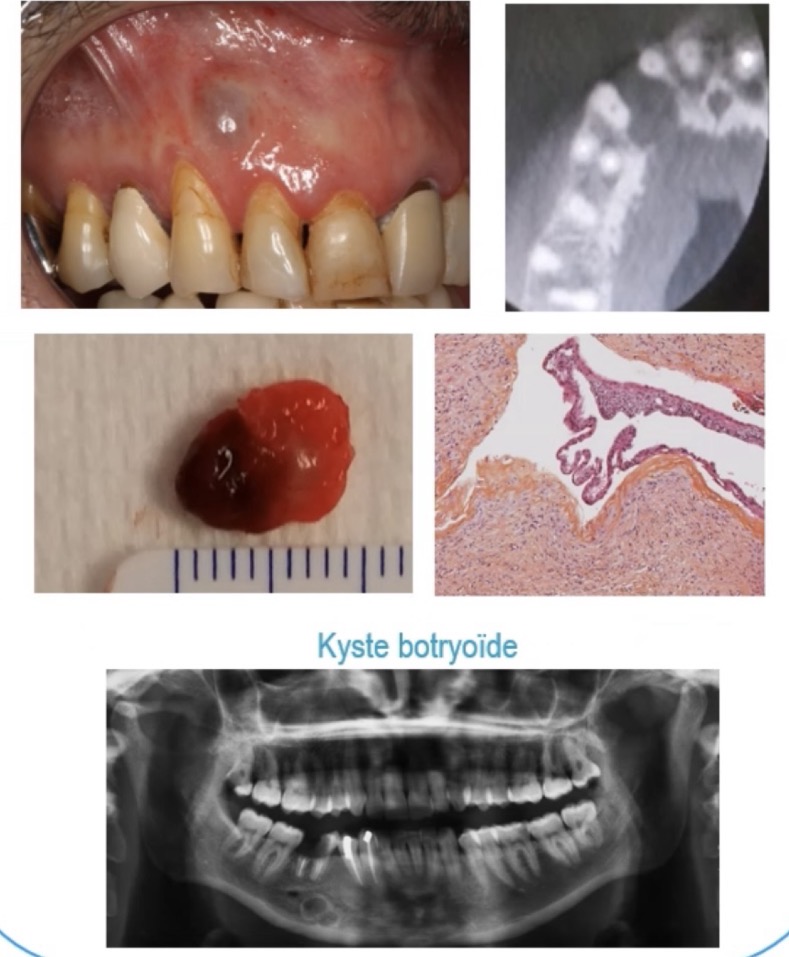

Kystes périodontal latéral